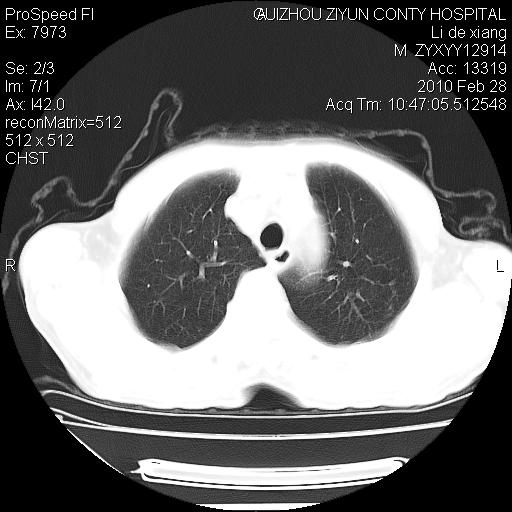

标题: CT24776:男 71Y 咳嗽咳痰胸痛两月,伴声音嘶哑。 [打印本页]

标题: CT24776:男 71Y 咳嗽咳痰胸痛两月,伴声音嘶哑。

左侧中央型肺癌伴左肺上叶阻塞性肺炎及节段性不张可能性大,建议纤支镜检查!

左侧中央型肺癌伴左肺上叶阻塞性肺炎及节段性不张可能性大,建议纤支镜检查!纵隔淋巴结转移.

左侧中央型肺癌伴左肺上叶阻塞性肺炎及纵隔淋巴结转移。

左肺门部肿块,伴左上肺斑块影,周边模糊,支持左肺中央型肺癌伴节段性不张及阻塞性肺炎,结合支气管镜检查。

左上叶支气管狭窄,阻塞性病变,肺门肿块,纵隔及肺门淋巴结增大,中央性肺癌